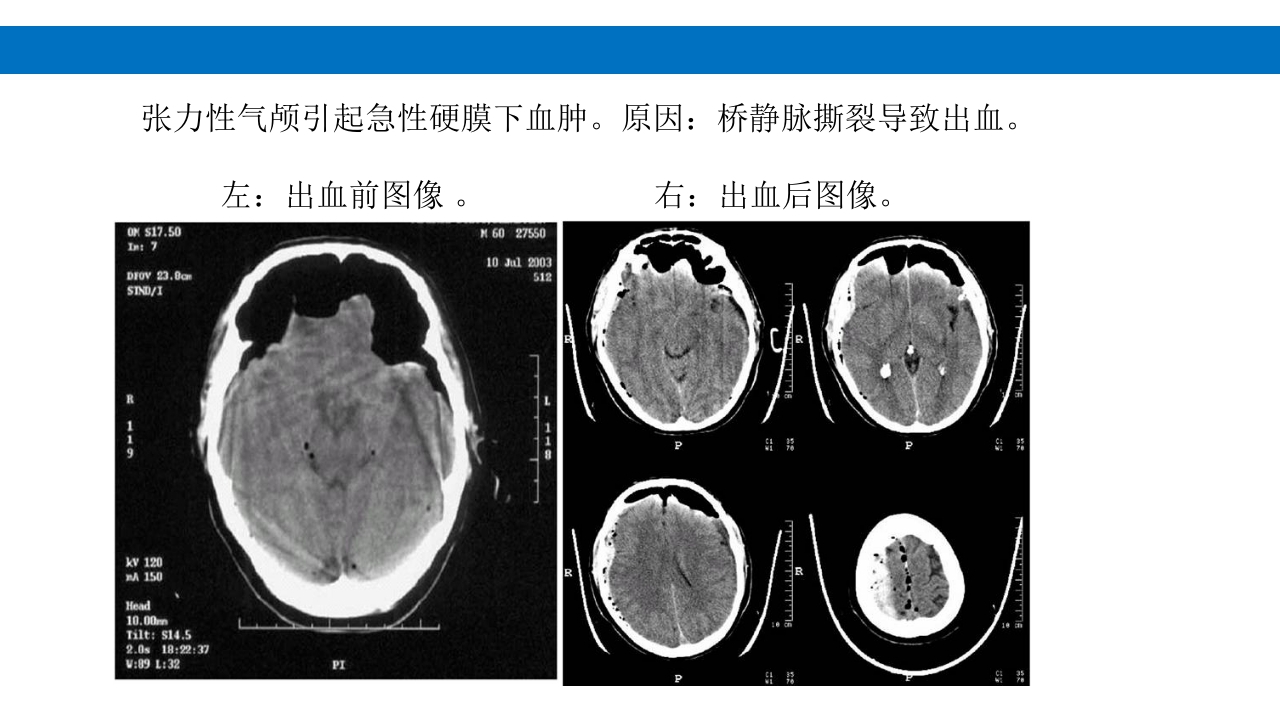

颅脑损伤的并发症及后遗症 讲解人:xxx 20XX年x月x日 1.颅骨骨髓炎 病因:为头皮软组织、中耳、乳突和副鼻窦等处炎性感染而经导 血管侵入颅骨内或颅脑开放伤感染所引起,亦可由菌血症后发生 的细菌栓子由血运转移至颅骨内。 影像学表现: 头部CT: 1.表现为不规则的蜂窝状骨质破坏区,主要位于板障,亦可累 及内外板。 2.破坏区内可见高密度的米粒状细小的高密度死骨。 3.周边可见骨质硬化增生,颅板外无骨膜反应。 4.局部的头皮可见软组织肿胀。 头部MRI: 由于受累部位细胞成分和水量增多,T1WI为低信号, T2WI为高信号,急性期边界不清,慢性期病灶局限, 边界清晰。MRI显示骨质破坏没有CT效果好。 治疗: 除应用抗菌药物控制感染外,当感染局限或已有死骨形成后, 应行手术切除感染...